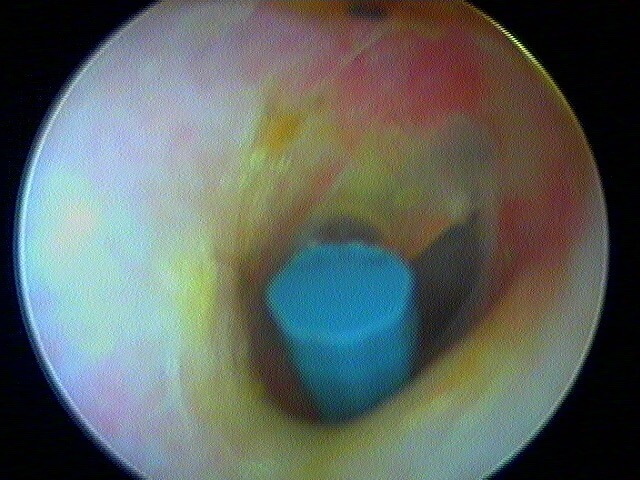

Pour comprendre la paracentèse, ici au laser diode sous A/L au cabinet:

Et la mise en place d'aérateur de type T-tube ici:

Parfois on retrouve l'aérateur englobé, sans conséquence: